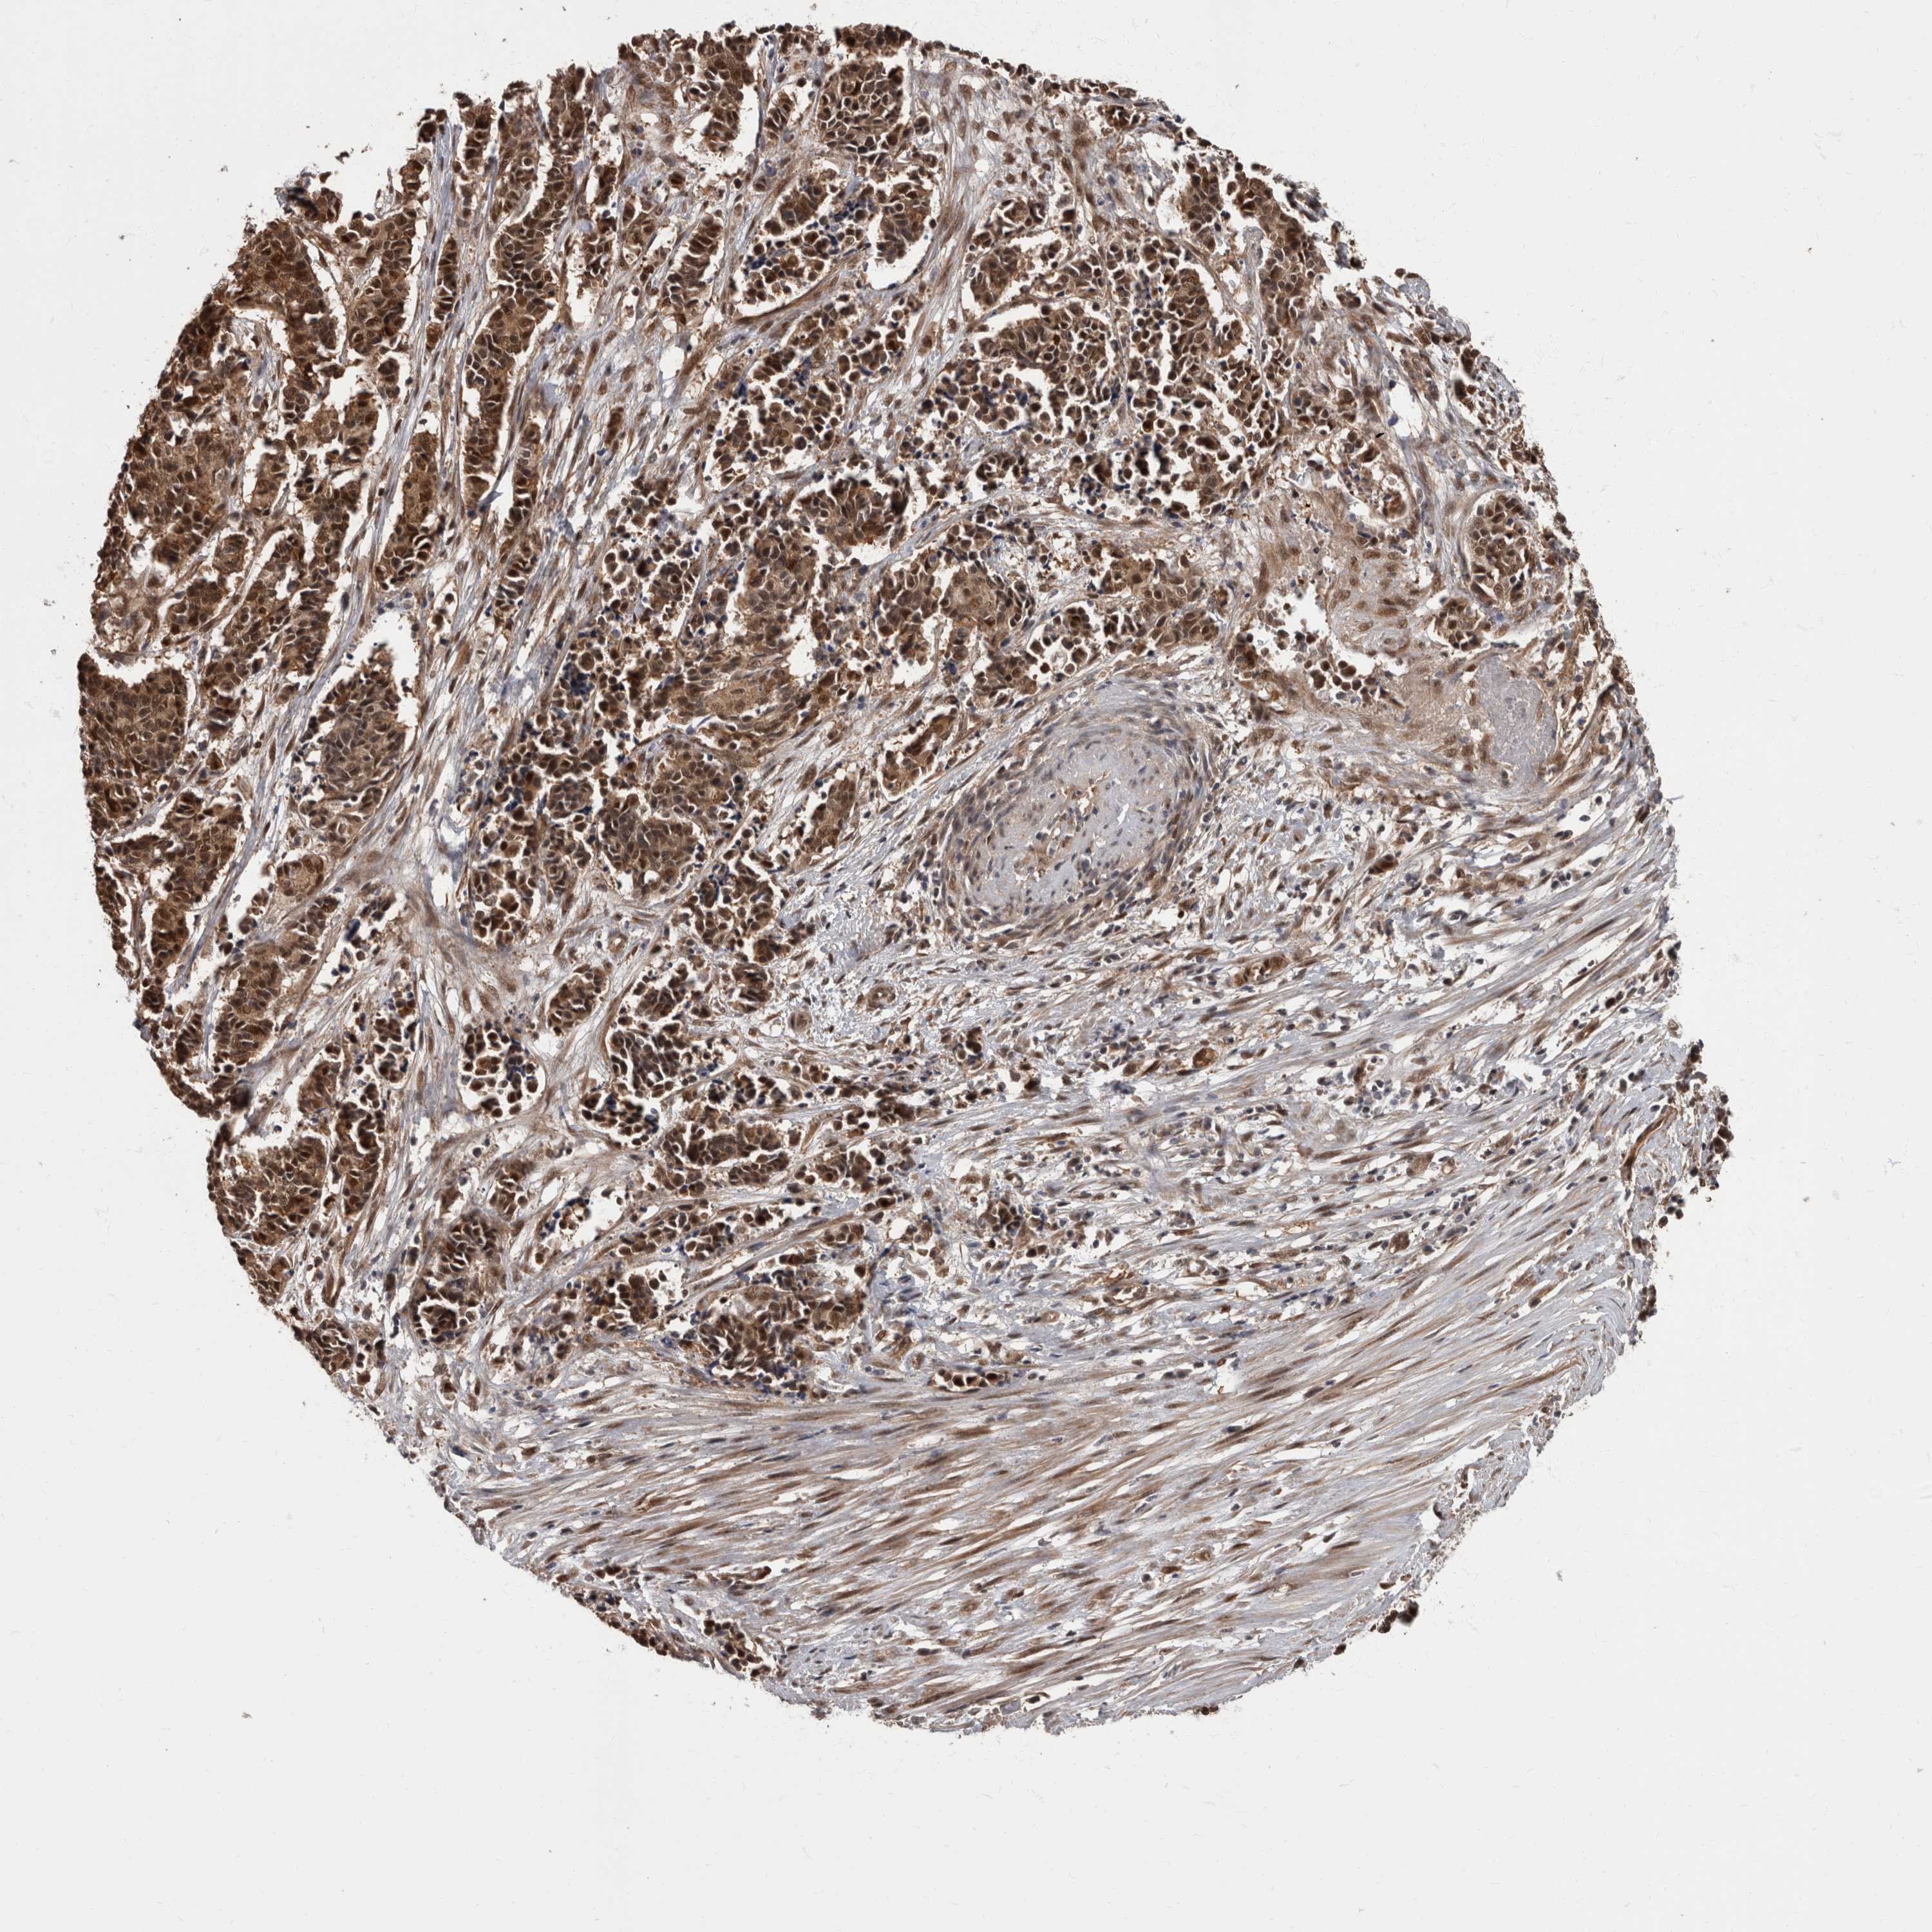

CERVICAL CANCER - Protein expressioni

A mouse-over function shows sample information and annotation data. Click on an image to view it in a full screen mode. Samples can be filtered based on level of antibody staining by selecting one or several of the following categories: high, medium, low and not detected. The assay and annotation is described here.

Note that samples used for immunohistochemistry by the Human Protein Atlas do not correspond to samples in the TCGA dataset.

Antibody stainingi

Antibody staining in the annotated cell types in the current human tissue is reported as not detected, low, medium, or high, based on conventional immunohistochemistry profiling in selected tissues. This score is based on the combination of the staining intensity and fraction of stained cells.

Each image is clickable and will lead to virtual microscopy that enables deeper exploration of all samples and also displays staining intensity scores, fraction scores and subcellular localization as well as patient and tissue information for each sample.

Antibody HPA026441

Antibody CAB013090

Staining

High

Medium

Low

Not detected

Intensity

Strong

Moderate

Weak

Negative

Quantity

>75%

75%-25%

<25%

None

Location

Nuclear

Cytoplasmic/membranous

Cytoplasmic/membranous,nuclear

Squamous cell carcinoma, NOS

Adenocarcinoma, NOS